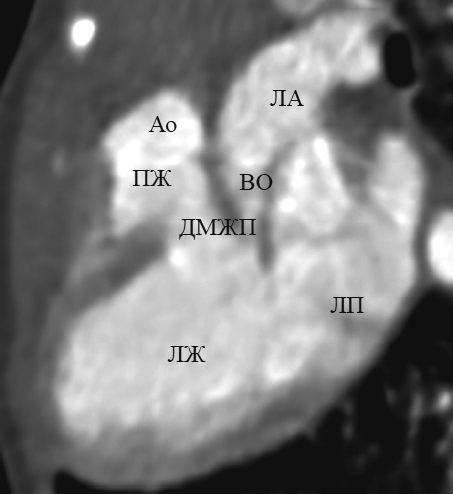

Достоверно визуализировать митрально-полулунное фиброзное продолжение, представляющее собой фиброзный контакт легочного клапана с митральным клапаном, при транспозиции удалось в 10 случаях (рис. 7, b). Дефект межжелудочковой перегородки визуализировался во всех случаях (рис. 7, c). В реформации по длинной оси левого желудочка удалось определить стеноз выходного тракта левого желудочка (рис. 8).

Рис. 8. В реформации по длинной оси левого желудочка при транспозиции магистральных сосудов определяется сужение выходного отдела левого желудочка. Ао — аорта; ЛА — легочная артерия; ВО — выходной отдел; ДМЖП — дефект межжелудочковой перегородки; ЛЖ — левый желудочек; ЛП — левое предсердие; ПЖ — правый желудочек

Fig. 8. Long-axis of left ventricle reformation in great arteries transposition: narrowing of the output portion of the left ventricle is determined. Ао – aorta; ЛА – pulmonary artery; ВО – the output portion; ЛЖ – left ventricle; ЛП – left atrium; ПЖ – right ventricle